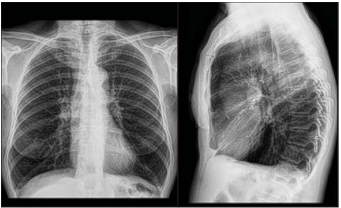

Paciente do sexo feminino, 64 anos, encaminhada para o ambulatório de clínica médica com história de tosse produtiva matinal diária com expectoração em pequena quantidade e de coloração mucóide há cerca de 3 anos. Refere ainda dispnéia progressiva. Observou que nos últimos meses, quando vai efetuar compras na feira (há menos de 100 metros de seu domicílio), precisa parar várias vezes por falta de ar. Ex tabagista (dos 15 aos 60 anos de idade), com uma média de 30 cigarros por dia. Além disso, residiu em casa com fogão de lenha até os 22 anos de idade. Nega internações ou uso de antibióticos. Ao exame físico, paciente responsiva, verbalizando.

Frequência respiratória de 16 incursões por minuto, tórax com aumento do diâmetro antero-posterior, expansibilidade diminuída e murmúrio vesicular diminuído difusamente. Ritmo cardíaco regular, bulhas hipofonéticas, frequência cardíaca de 89 batimentos por minuto. Pressão arterial de 120x80mmhg. Peso 50kg. Altura 1,65m. Trouxe exames realizados há aproximadamente 20 dias (radiografia de tórax abaixo). Espirometria com relação volume expiratório forçado no primeiro segundo (VEF1) / capacidade vital forçada (CVF) abaixo de 0,7 e ausência de resposta significativa a broncodilatador. VEF1 da paciente foi 55% do valor predito.